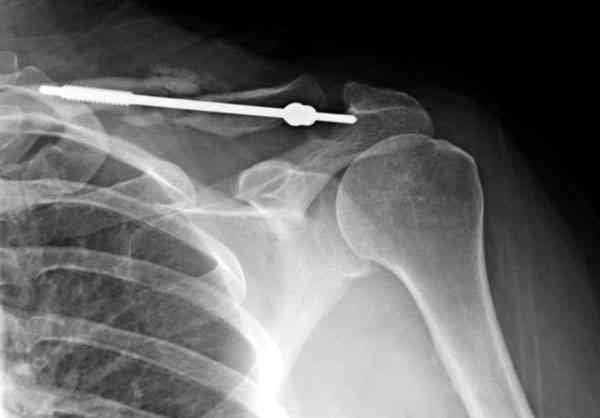

Недавно разбирали случай ложного сустава.

45 летная женщина после автоаварии, алкоголь 163 и 20 летним стажем курения.

Консервативное лечение, через 8 мес. операция Rockwood pin с костной пластикой в нашем городе другим врачом. После 8 недели падение, гвоздь удален оперирующим хирургом, больная направлена к нам. Фиксация реконструктивной пластиной с трикортикальным графтом, добавлен BMP-2. Для стабилизации фиксацию провели через акромион.

Вот уже два месяца больная также продолжает жаловаться на боли, буквально на днях удалили акромиальную часть пластины с специальной пилой с алмазным покрытием для медицинского металла. До сих пор судьба ложного сустава неизвестна....